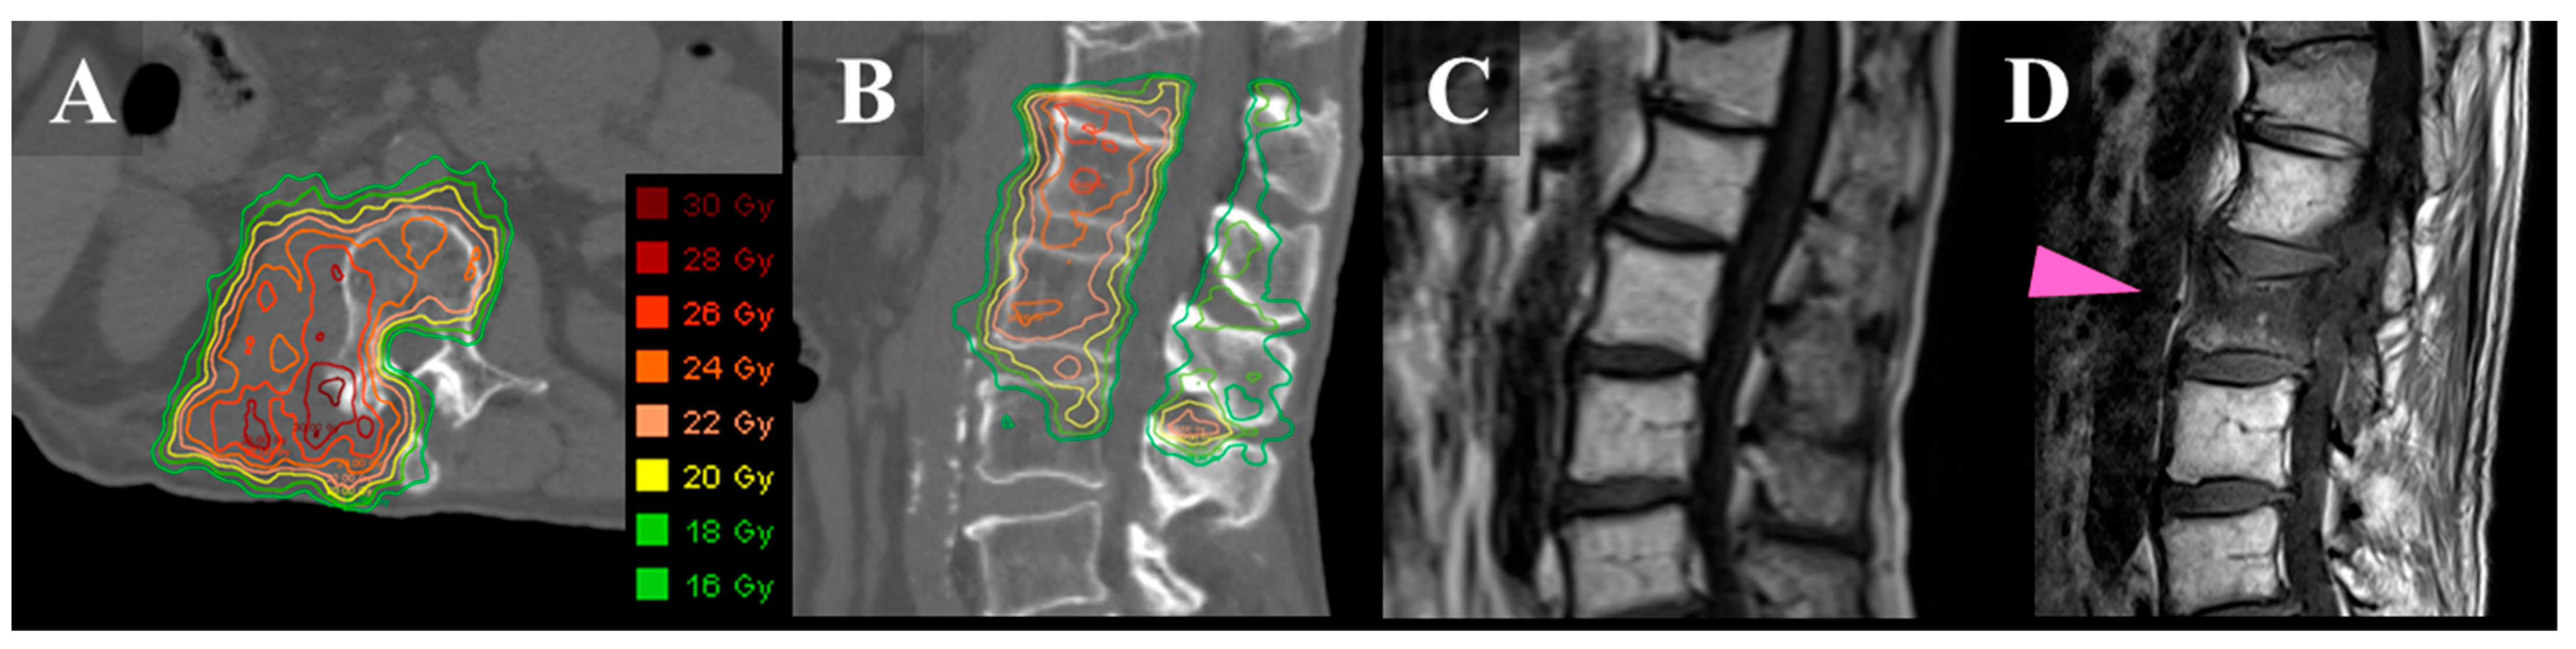

A DualScrew Technique for Vertebral Compression Fractures via Robotic Compression Fracture Calcitonin This review concluded that calcitonin appeared effective in the management of acute pain associated with acute osteoporotic vertebral. Vertebral compression fractures are the most common complication of osteoporosis, with 700,000 cases reported every year in the united states. Elcatonin, eel calcitonin, can also be used to treat acute back pain in patients with osteoporotic vertebral fractures. Calcitonin is another effective. Compression Fracture Calcitonin.

An 80yearold female patient with thoracic 12 vertebral compression Compression Fracture Calcitonin Calcitonin is another effective medication used for pain management in compression fractures, especially when they. High quality evidence was found supporting the efficacy of salmon calcitonin with reduction in compression fracture pain after 1. Vertebral compression fractures are the most common complication of osteoporosis, with 700,000 cases reported every year in the united states. Elcatonin, eel calcitonin, can also be. Compression Fracture Calcitonin.

From journals.sagepub.com